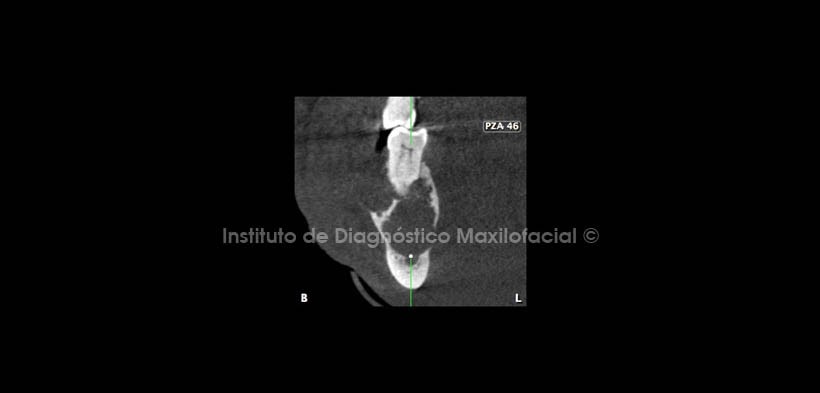

En cortes transaxiales, corte sagital y reconstrucción en 3D se aprecia claramente reabsorción radicular en piezas 48, 47 y 46 (Fig. 6-10).